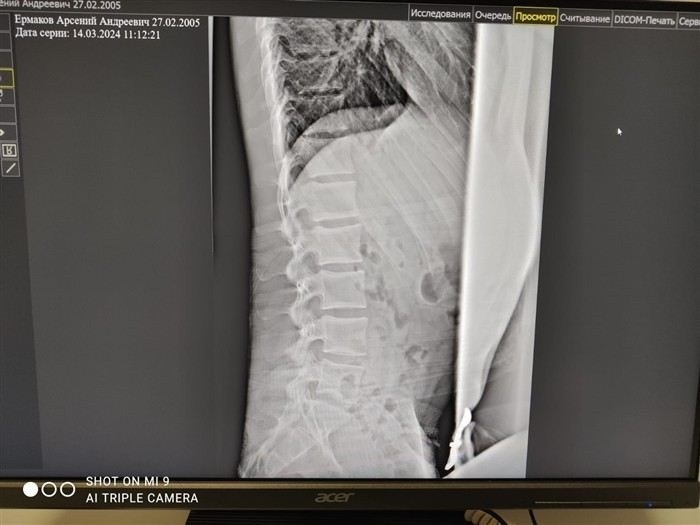

Для определения возможности службы медицинская комиссия основывается на функциональных нарушениях, выявленных при обследовании, а также на рентгеновских снимках, которые показывают степень повреждения шейного отдела. Нестабильность шейных позвонков, кифоз и другие симптомы могут повлиять на решение, если это затрудняет выполнение норм службы.

Кроме того, медицинская комиссия анализирует симптомы заболевания и степень их выраженности. Для диагностики остеохондроза и других заболеваний важно иметь рентгеновские снимки, которые помогут врачу определить, насколько сильно заболевание влияет на здоровье пациента. В некоторых случаях для подтверждения диагноза могут быть назначены дополнительные обследования. На основе полученных данных, комиссией принимается решение, которое зависит от степени заболевания и его влияния на способность к службе в армии.

Первым шагом является сбор медицинских документов, которые подтверждают наличие заболеваний, таких как остеохондроз или кифоз, а также другие болезни позвоночника. Важными являются заключения рентгенолога, данные о наличии нестабильности позвоночника, а также симптомы, которые свидетельствуют о трудностях при выполнении военной службы. Для подачи апелляции понадобятся копии медицинских документов, включая рентгеновские снимки, заключения специалистов и подробное пояснение симптомов.

Для подтверждения необходимости отсрочки необходимо предоставить медицинские документы, включая заключения специалистов и результаты рентгеновских исследований. Важным фактором является степень заболевания и его влияние на способность выполнять физические нагрузки, характерные для службы в армии. В случае серьезных заболеваний шейного или поясничного отдела позвоночника, сопровождающихся сильными болями или ограничением подвижности, призывник может быть освобожден от службы или переведен в запас.